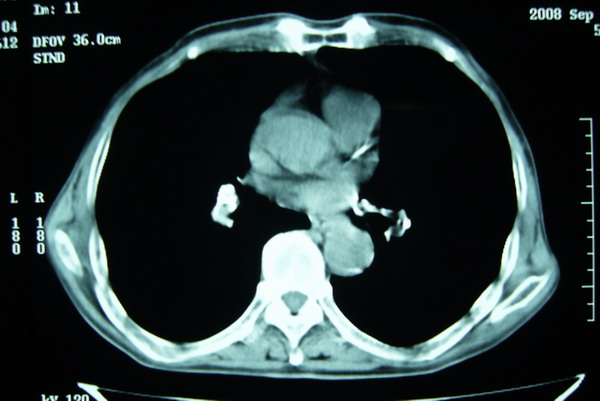

标题: CT15579:男 86岁 咳嗽 咳少量白痰 发热2天 吸烟史60年 [打印本页]

标题: CT15579:男 86岁 咳嗽 咳少量白痰 发热2天 吸烟史60年

右肺上叶巨大软组织肿块,轮廓不规则,纵隔内有肿大淋巴结,首先考虑肺癌。

右上肺一不规则团块,边缘有分叶和毛刺,纵隔有淋巴结肿大。右肺周围性肺癌首先考虑。